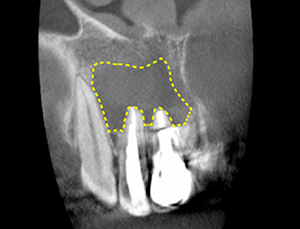

The area I thought I had cleaned up to the apex of the root was actually the intersection area far above the apex. (Figure 3)

For this reason, in a patient with a large amount of dissolved bone around the root(Fig. 6),